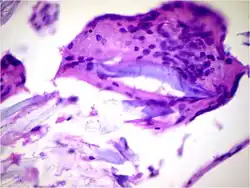

Infiltrative ductal carcinoma | Atypical cells with moderate amount of eosinophilic cytoplasm and round to oval dark nucleus with moderate pleomorphism (Papanicolaou, 400X) | Category: Histopathology of invasive carcinoma of no special type | invasive breast carcinoma |

![]() |